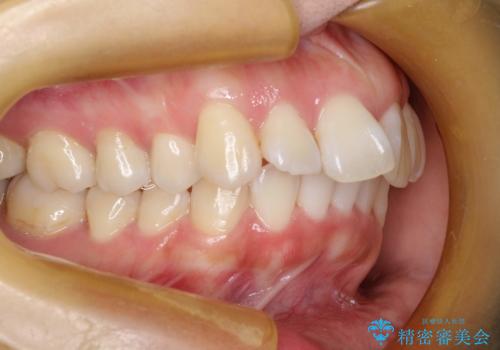

抜歯をして前歯を下げ、ガタつきを取り除く ワイヤー矯正

- 30代女性

- 上顎両側第1小臼歯、下顎左側第2小臼歯の3本を抜歯、ラビアルのワイヤー矯正を計画した。

抜歯矯正は抜歯にできたスペースをつかい、前歯を積極的に下げたり、大きなガタつきを取り除くことができますが、その分時間がかかります。